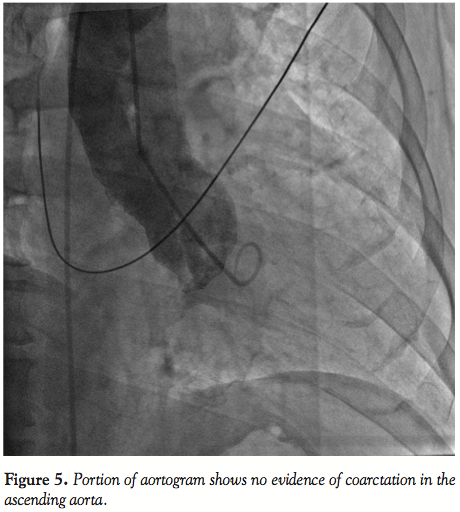

Imaging of the right coronary and circumflex arteries revealed no significant lesion. The left ventricular ejection fraction was normal. The injection into the LIMA showed marked increased diameter (Figure 1) with unusually long collaterals extending to the left common femoral artery (Figure 2). There was a total occlusion of the left common femoral artery (Figure 3) with reconstitution of the common femoral artery from the LIMA collaterals (Figure 4). There was no evidence of coarctation in the proximal ascending aorta identified of the aorta on this or prior coronary angiography studies (Figure 5).